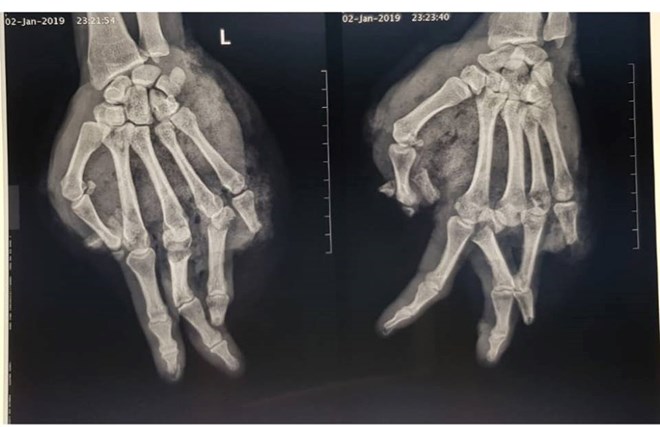

Ảnh chụp phim X-quang bàn tay của bệnh nhân. (Ảnh: BVCC)

Bác sỹ Vũ Hữu Trung - Khoa Khoa Chấn thương Chi trên và Vi phẫu thuật, cho hay, qua quá trình thăm khám cho thấy, bệnh nhân bị tổn thương vết thương phức tạp, dập và lóc da, bầm dập nặng phần mềm bàn tay, dập nát ngón I, V và đốt 2,3 ngón IV; gãy hở nền xương đốt 1 ngón III, IV.